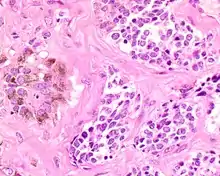

| A bone resection sample showing the pigmentation below the surface in a melanotic neuroectodermal tumor of infancy | |

Microscopic

The tumor is usually very well circumscribed but not encapsulated. There are two cell types present (biphasic), arranged in alveolar or tubular configurations.

There are centrally located, small, darkly staining cells comprising the majority of cells. These cells have a fibrillary cytoplasm surrounding round nuclei with coarse and heavy nuclear chromatin. These cells are surrounded by much larger polygonal cells that have open nuclear chromatin and abundant opaque cytoplasm that has granular melanin pigment.

There is usually no hemorrhage, necrosis or increased mitoses.[1][4]